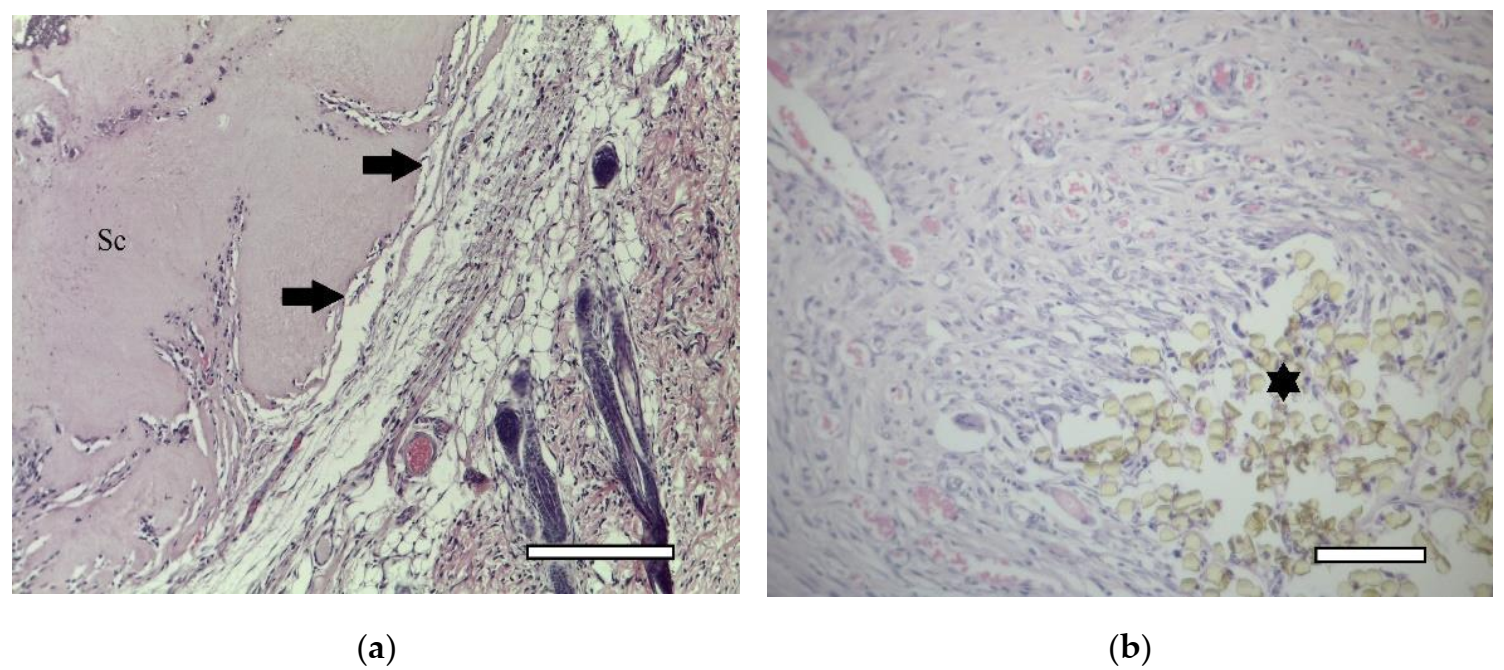

2.5.1. 1st Group (Collagen + dECM)